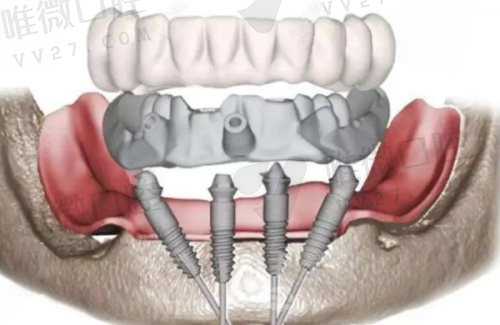

优势亮点:非常注重患者体验感,有专属诊疗分区。肿 瘤术后修复、齿槽骨骨量不足患者也可在这里做延迟种植、骨粉植入等个性化方案。

种植牙类型:瑞士ITI、韩国OSSTEM等多型号价格公开透明,适合中端追求品质派。